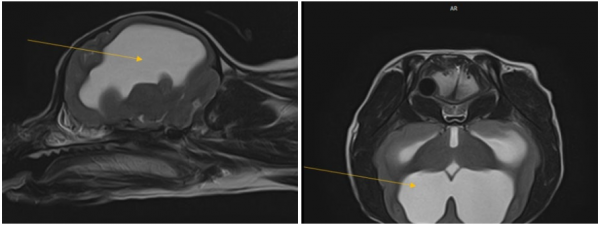

② 뇌 기형 및 수두증

- 후두골 기형(Occipital malformation) 으로 인해 소뇌 압박

- 연수의 구부러짐 (medullary kinking) 및 CSF 흐름 장애 발생

- 제1경추의 후방 구조가 두개골과 겹치는 atlanto-occipital overlapping(AOO) 소견도 동반되어,

- 추가적인 뇌압박이 유발

- 뇌실 확장(ventriculomegaly) 및 선천성 수두증(hydrocephalus) 확인

- 다수의 두개골 결손(calvarial defects) 도 관찰되었으나, 뇌 탈출은 없는 상태